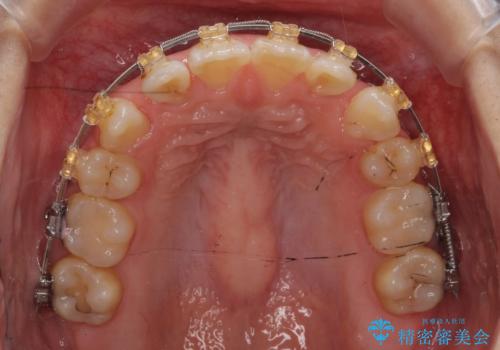

矯正治療をおすすめし、ちょうど虫歯がひどい歯は抜歯して前歯を下げました。

下顎の大臼歯が前に倒れこんでいたため、矯正用ミニスクリューで後ろに起こしています。